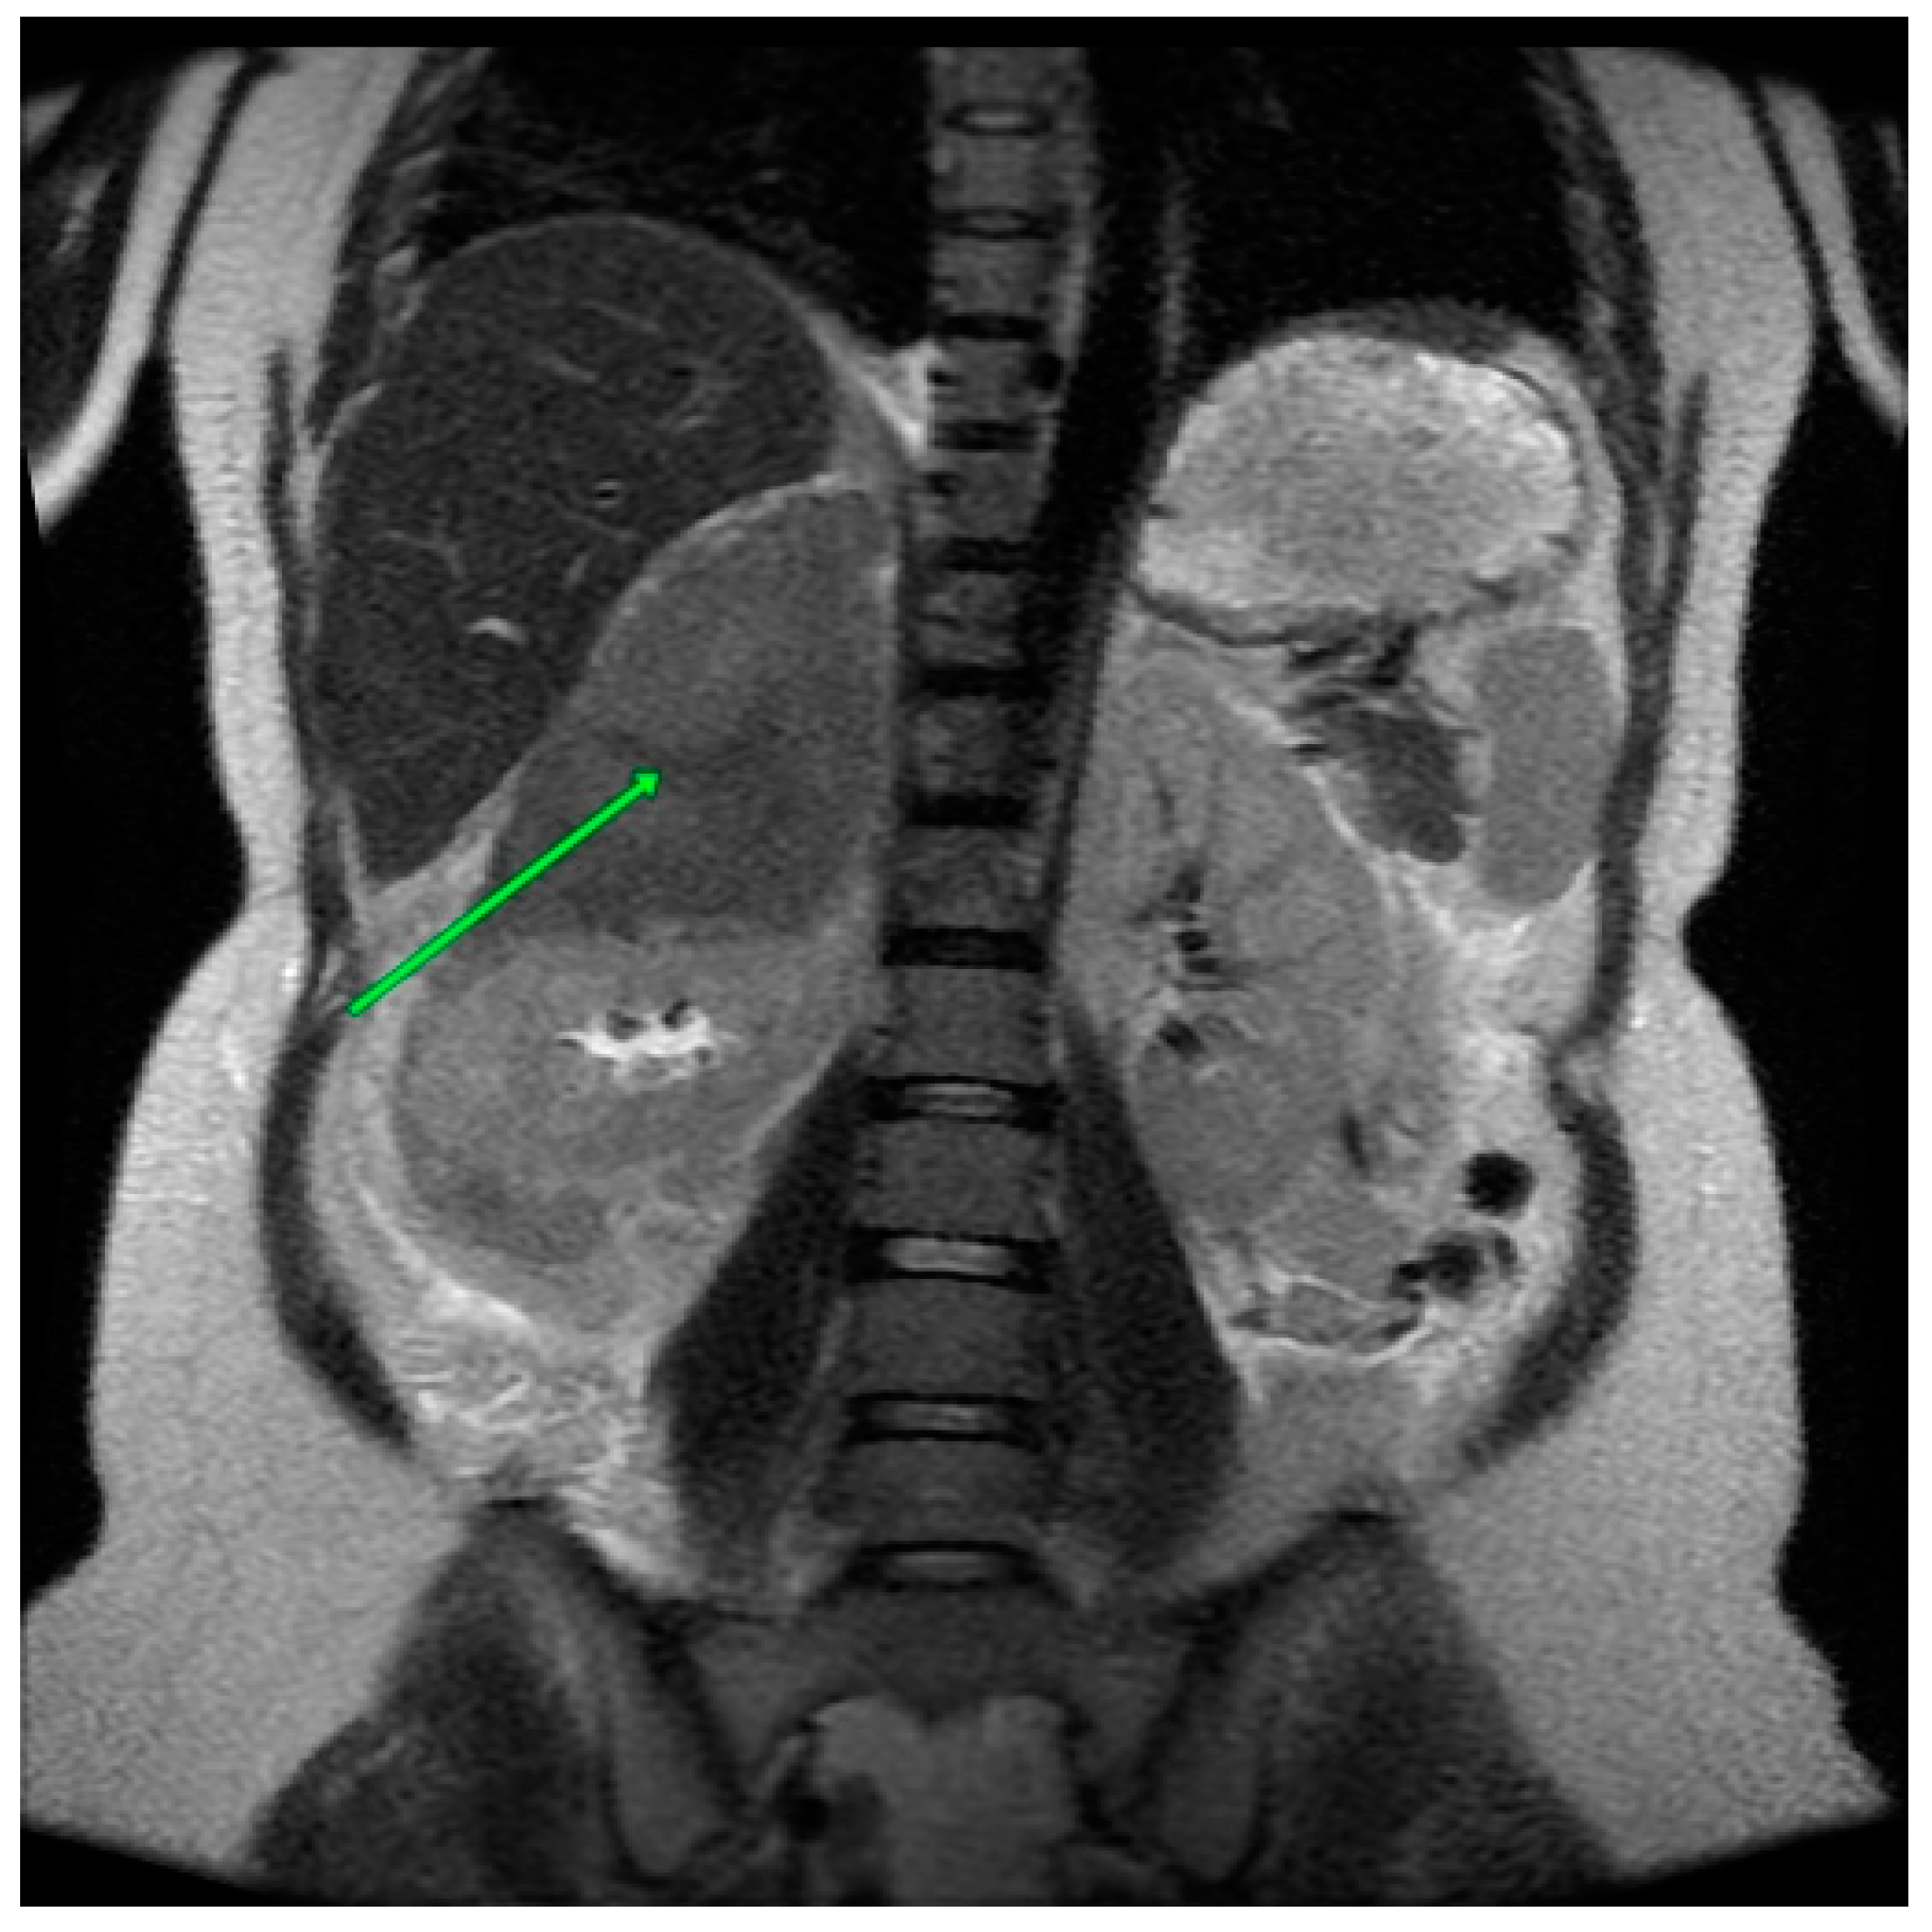

A further ultrasound was performed the following day. It demonstrated the presence of a partially liquefied hematoma in the projection of the right adrenal gland, with a measured volume of 93 × 56 × 63 mm (Figure 2).

Figure 2. Abdominal ultrasound. A hematoma is visible in the projection of the right adrenal gland.